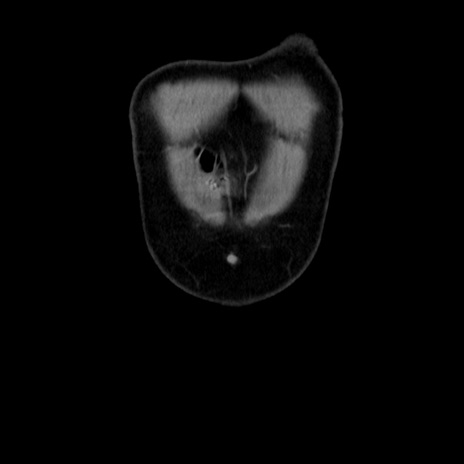

横断像